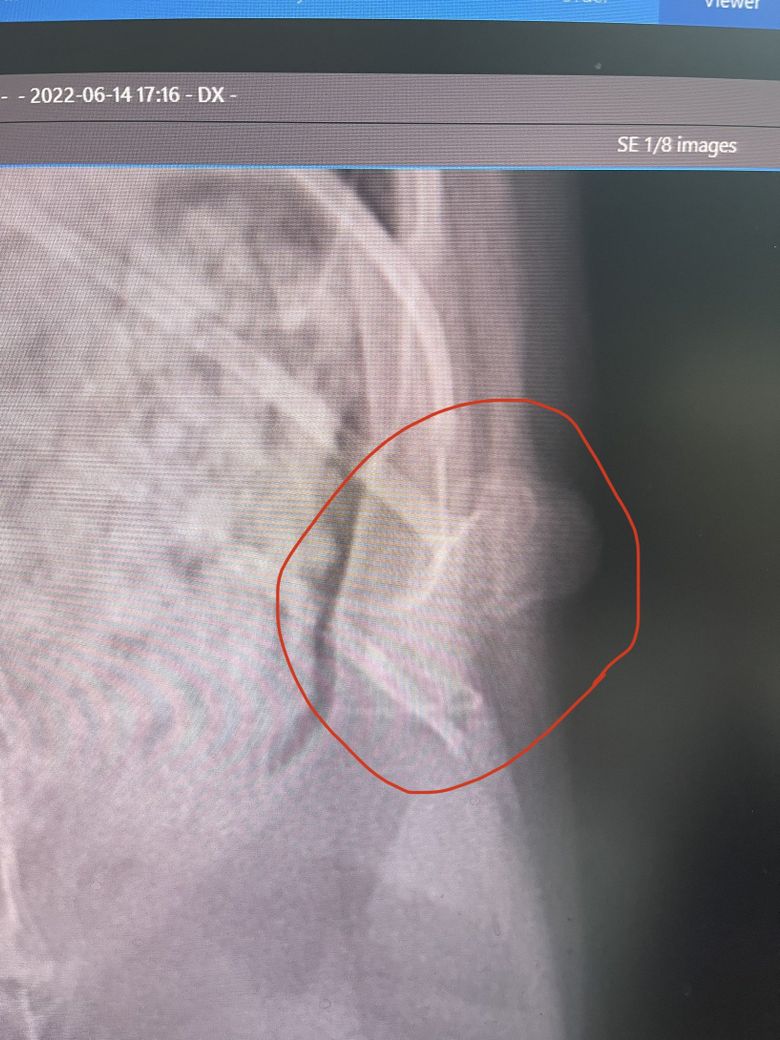

얼마전부터 왼쪽옆구리에 볼록하게 뼈같은게 만져져서 병원에서 엑스레이 촬영을 해보았는데요 의사선생님이 확실하게 말씀을 못해주시네요.. 뼈가 기형일수도있고 아니면 종양일수도 있다고 하셔서 걱정이됩니다

사진상으로 확인될지모르나 관심있게 봐주세요..ㅠ

1세 정도의 어린 고양이의 늑골, 늑연골 부분에 이런 뼈 덩어리가 관찰되는 경우에는 일차적으로

다발성 연골외골증 ( multiple cartilaginous exostosis , 다발성 연골뼈돌출증 ) 을 1차적으로 의심합니다.

이 질환은 어린 나이에서 발생하고, 늑연골 연접부가 호발 위치이기 때문이지요.

다시 말해 "다발성" 질환이기 때문에 손에 만져지는 늑골 부분이 아닌 척추, 두개골 등 다른 뼈들에도 비슷한 골 증식 병변이 있을 수 있어 우선 전신 엑스레이 검사를 통해 다른 부분의 병변을 찾아볼 필요가 있다는 것이지요.

물론 다발성 연골외골증의 최종적인 확진은 이렇게 엑스레이 사진으로 하는것이 아니라 조직검사를 통해 해야 하는것이라 지금 말씀 드리는건 가진단일 뿐입니다.